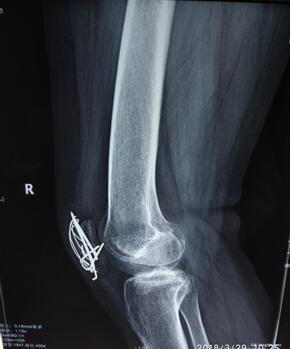

患者术前膝关节正侧位X线

孙主任通过查体和观看膝关节X线,得出患者是膝关节骨折术后关节僵硬,可以关节镜下微创松解治疗。住院医师申福国做术前查体,发现患者右侧膝关节伸约0°,屈曲约32°,几乎为完全僵硬关节,孙主任组织科内微创治疗小组进行病例讨论,对患者术中手术方案及术后康复治疗均做出完整规划。